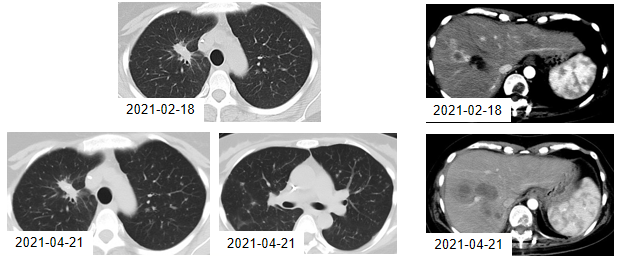

2021年3月17日、2021年4月12日,患者继续接受2周期的贝伐珠单抗联合免疫治疗维持治疗。2021年4月21日,CT复查结果显示:右肺上叶肺癌伴双肺多发转移,肝脏病灶增多增大,考虑疾病再次进展。2021年5月7日,患者将方案调整为替雷利珠单抗联合安罗替尼。

图11. 2021年2月18日与4月21日的CT检查结果

替雷利珠单抗联合安罗替尼治疗2周期后,复查胸部CT显示:双侧胸腔积液,双肺多发转移病灶增大,肝脏病灶增大。

图12. 2021年4月21日与6月15日的CT检查结果